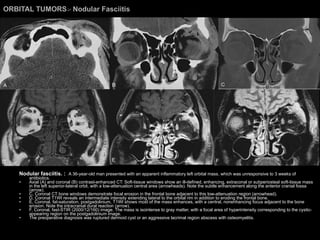

Nodular Fasciitis Common fibrous tumor. Found elsewhere in the limbs and trunk of adults. Head and neck involvement = more commonly in infants and children. Orbital involvement may develop in the lid, conjunctiva, Tenon’s capsule, or the deep orbit. CT and MR imaging findings are nonspecific. Similar to those of aggressive fibromatosis. Best treated with complete excision. Recurrence rate of 1-2%.

ORBITAL TUMORS >  Nodular Fasciitis Nodular fasciitis. :  A 36-year-old man presented with an apparent inflammatory left orbital mass, which was unresponsive to 3 weeks of antibiotics.  Axial (A) and coronal (B) contrast-enhanced CT: Soft-tissue windows show an ill-defined, enhancing, extraconal or subperiosteal soft-tissue mass in the left superior-lateral orbit, with a low-attenuation central area (arrowheads). Note the subtle enhancement along the anterior cranial fossa (arrow).  C, Coronal CT bone windows demonstrate focal erosion in the frontal bone adjacent to this low-attenuation region (arrowhead).  D, Coronal T1WI reveals an intermediate intensity extending lateral to the orbital rim in addition to eroding the frontal bone.  E, Coronal, fat-saturation, postgadolinium, T1WI shows most of the mass enhances, with a central, nonenhancing focus adjacent to the bone erosion. Note the intracranial dural reaction (arrow).  F, Coronal, fast-STIR (2000/12/160) image. The mass is isointense to gray matter, with a focal area of hyperintensity corresponding to the cystic-appearing region on the postgadolinium image.  The preoperative diagnosis was ruptured dermoid cyst or an aggressive lacrimal region abscess with osteomyelitis.